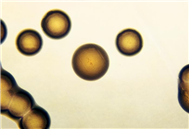

(세균) Neisseria gonorrhoeae

출처:http://phil.cdc.gov/phil/details.aspID#2649, CDC/W. Jerry Brown

• 특 성 :Neisseriaceae과, 그람음성, 쌍알균,포자 형성 안함